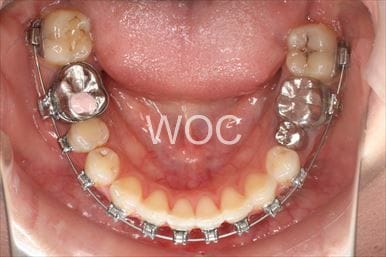

治療中3

- 年齢:20歳女性

- 主訴:出っ歯が気になる

- 基本矯正料金:120万円

- 治療期間:1年7ヶ月

- 抜歯部位:上顎両側第一小臼歯